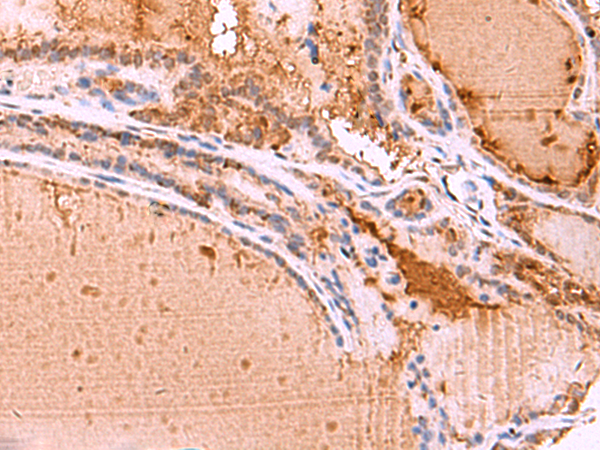

IHC positive control:

Human prostate cancer

IHC Recommend dilution:

20-100